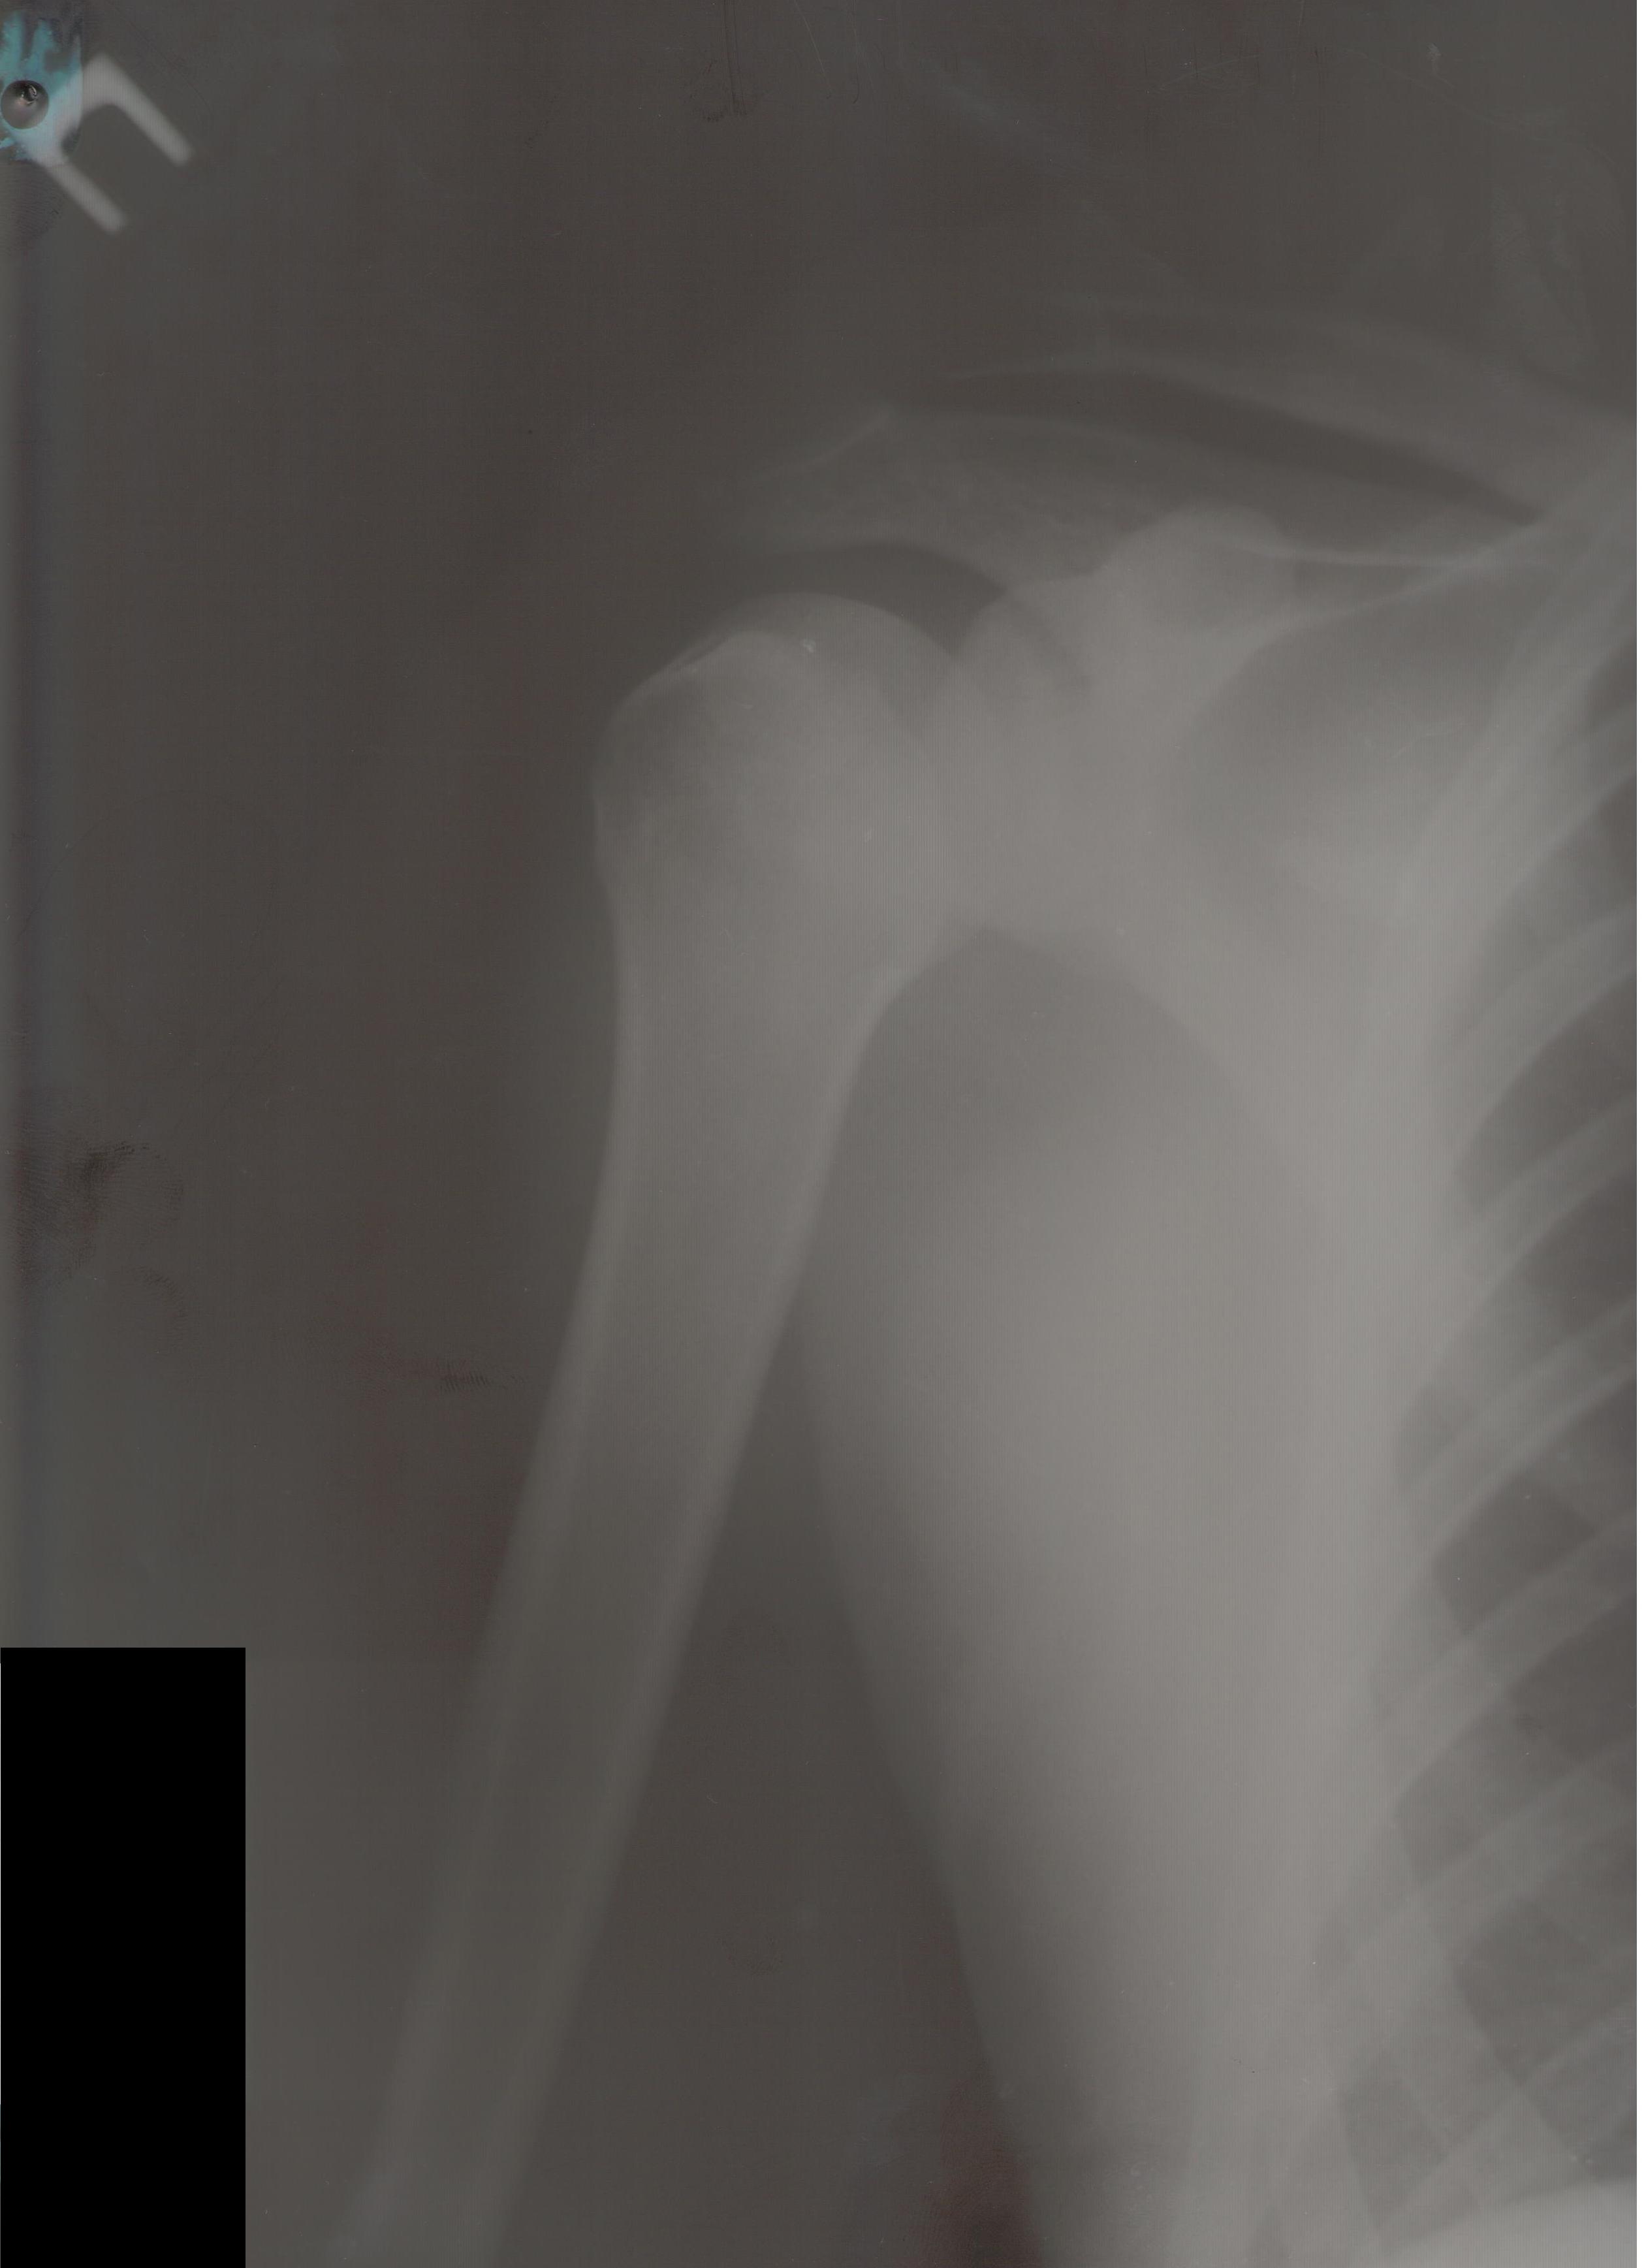

Уважаемые коллеги! 12.08.2014 поступил молодой человек 28 л. спортивного сложения (активно занимается "железом") - травма уличная - получил удар током 220В от электронасоса, затем, по всей видимости, упал на правое плечо (изначально факт падения не озвучивался). В связи с электротравмой и срывом ритма госпитализирован в ОАИТ. По стабилизации состояния начал жаловаться на интенсивные боли в правом плечевом суставе. Выполнена Р-графия правого плечевого сустава, дежурный травматолог расценил видимый костный фрагмент как отрывной перелом либо головки, либо суставного отростка лопатки; иммобилизация правой верхней конечности осуществлена бандажом. На следующий день боли в правом плечевом суставе сохранялись, осмотрен клинически - заподозрен задний вывих плеча, на повторной прямой Р-грамме ничего существенного, снимок с выведением большого бугорка не удался из-за ограничения наружной ротации. Затем выполнена КТ - диагностирован переломо-вывих правого плеча. Под общим обезболиванием вывих закрыто устранен, иммобилизация осуществлена гипсовой повязкой. Возникает вопрос: что делать дальше? Необходимость оперативного вмешательства вроде бы  очевидна, но вот его объем?  Пока планируется элевация импактированного фрагмента, остеосинтез всего этого на PHILoSе. Второе мнение - синтез фрагмента головки и малого бугорка винтами (Герберта?), фиксация большого бугорка (подшивание). Либо сочетание этих способов... Время вроде бы поджимает, хотелось бы узнать видение ситуации уважаемым сообществом.